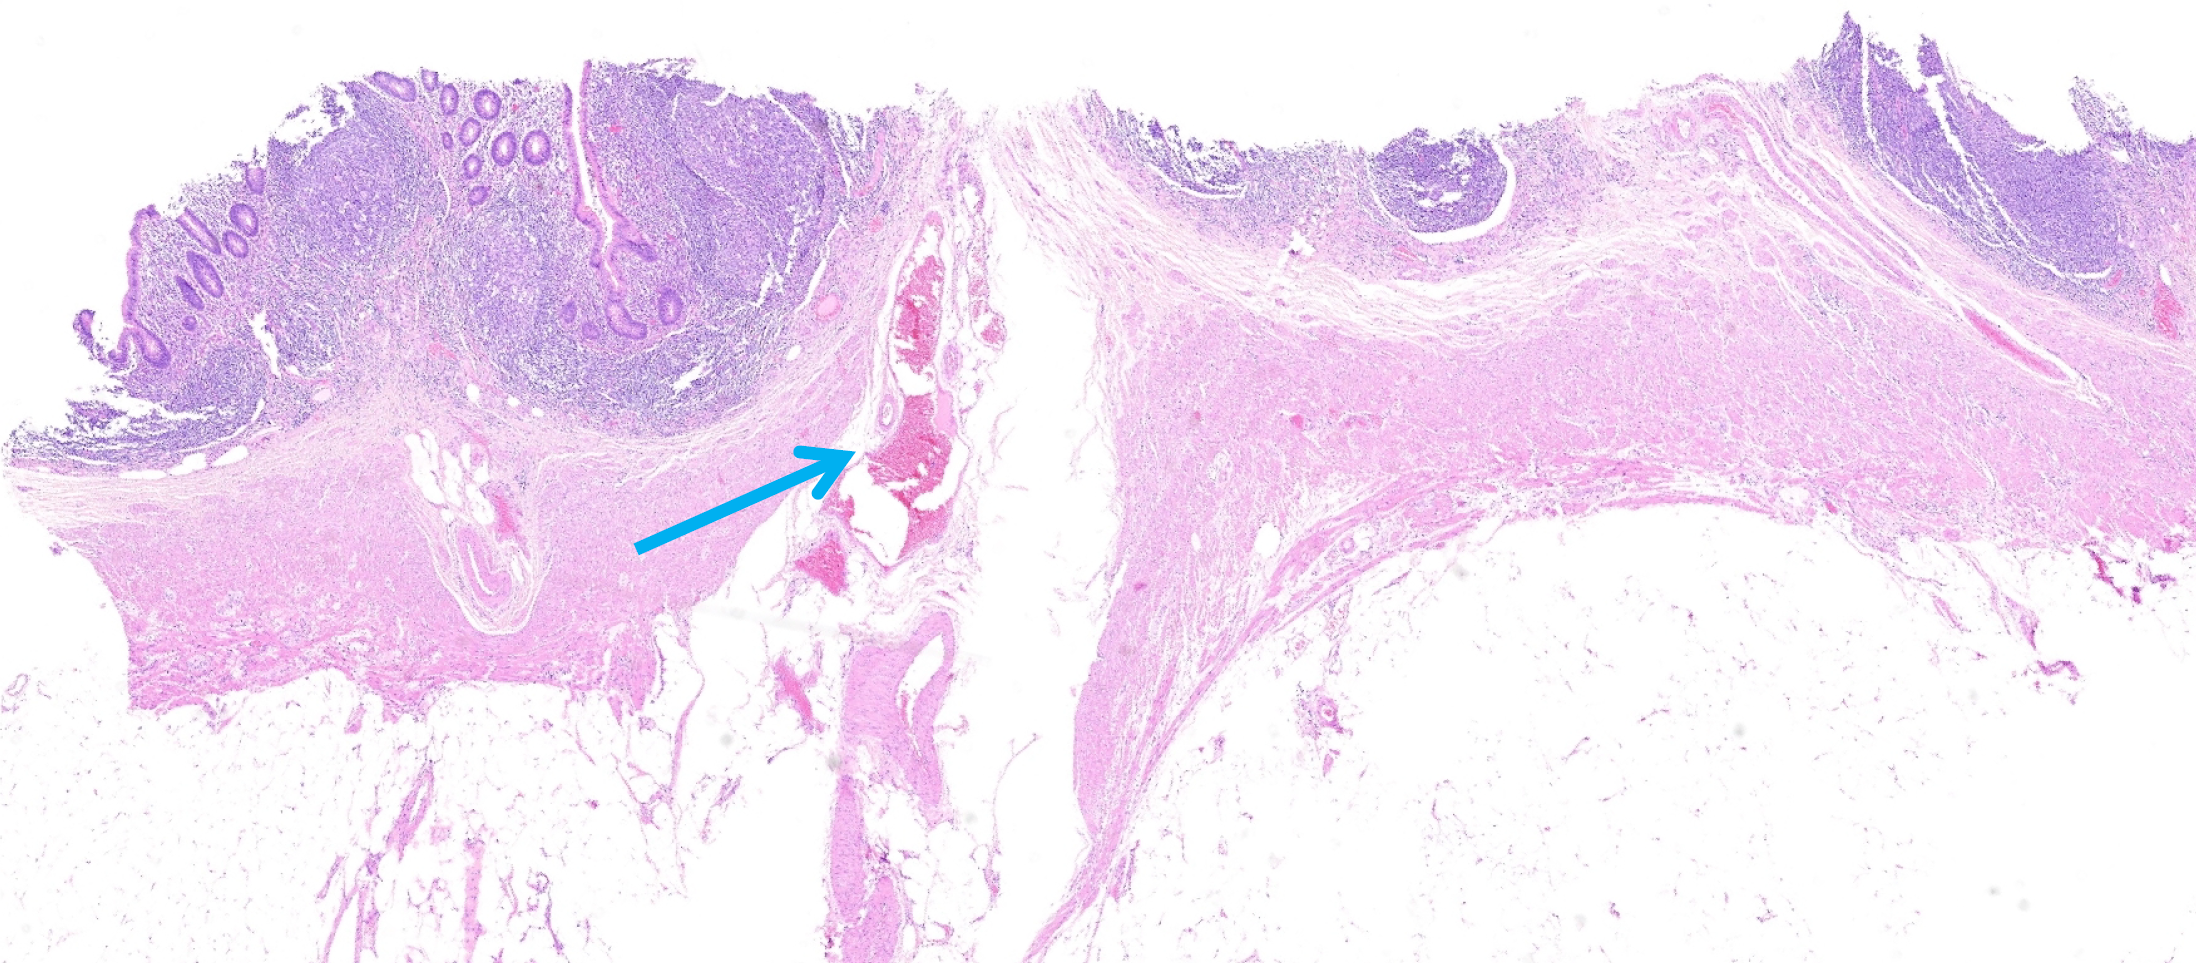

On January 7, 2025, colonoscopy was performed after bowel preparation which revealed a small amount of dark red blood in the colon and minimal bright red blood in the terminal ileum. After repeated water flushing, the mucosa of the terminal ileum appeared smooth, with no blood in the proximal intestinal lumen. On careful examination, fresh bleeding was noted from the appendiceal orifice (Figure 1). Following colonoscopy, emergent computed tomography angiography (CTA) was performed, which demonstrated active bleeding at the appendiceal orifice (Figure 2).

Figure 2

Figure 2 Abdominal computed tomography angiography reveals active appendiceal bleeding. A: Computed tomography scan without contrast showing no abnormalities (arrow); B: The arterial phase showing an active contrast leak in the appendix (arrow); C: The venous phase showing progressive enlargement of the contrast leak (arrow).